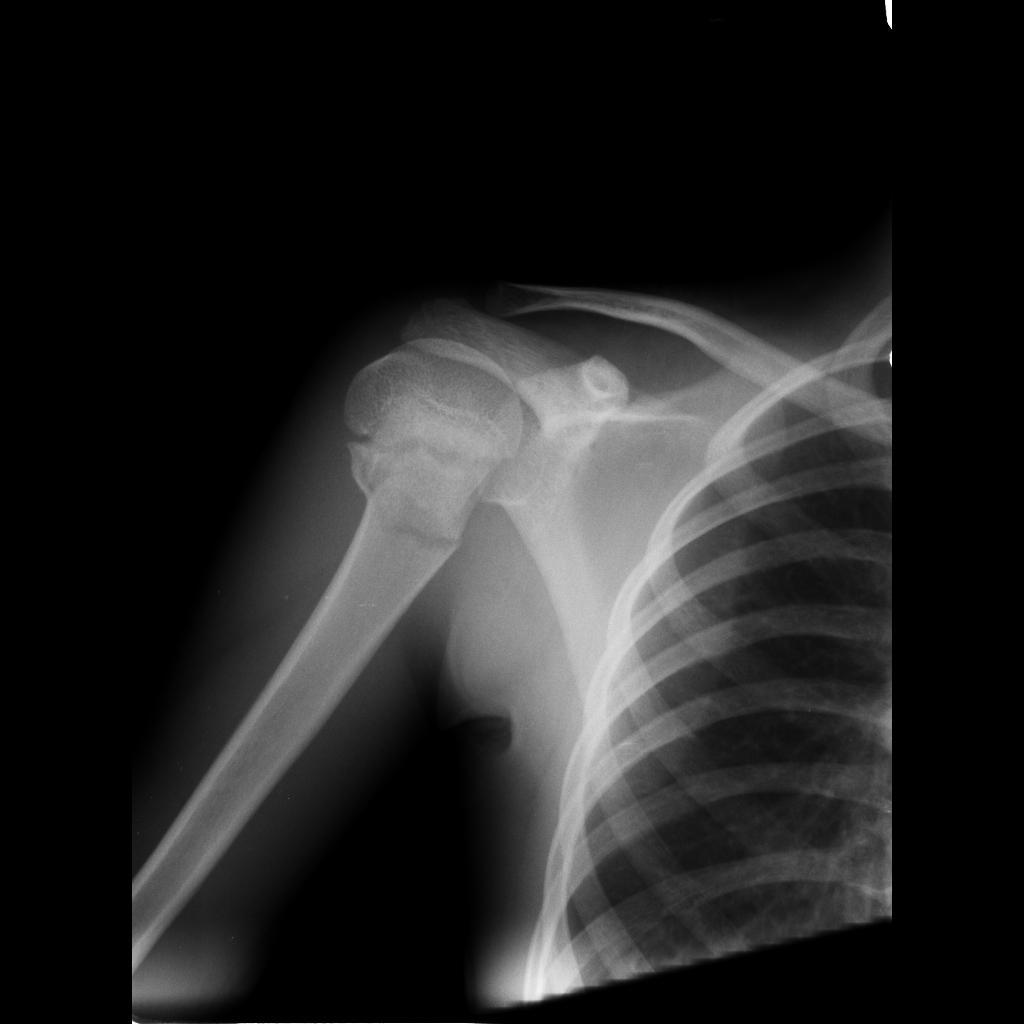

What type of injury can be seen?

Surgical neck of humerus fracture

What nerve injury can be associated with a surgical neck fracture? How can this be tested?

Axillary nerve injury

Motor:

Sensory: